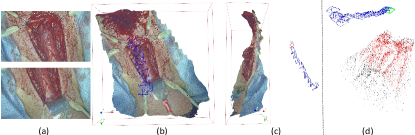

We first qualitatively tested our 3D reconstruction method on phantoms and ex vivo tissues, including porcine stomachs and livers. We used a KARL-STORZ stereo laparoscope (model number TipCam 26605AA) with a resolution of to capture stereo videos and performed the proposed 3D reconstruction method on the videos. The candidate disparity values for performing ZNCC matching are between and pixels. Details of the videos are provided in Tab. I. The results of our ex vivo qualitative experiments are shown in Fig. 8. Since down-sampling is not included in the reconstruction process, the obtained 3D models have the same resolution as the input image, which usually include millions of points and are able to provide rich details of the surface texture. Our results qualitatively look promising and accurate. We also employed ORB-SLAM2 [6] for comparison, which is one of the most famous open-source SLAM methods. In order to handle low texture, the key parameters of ORB-SLAM2 were set as follows: the number of feature points is 3000 per image, and the threshold for detecting FAST corner is 1. As shown in Fig. 8(a) and (c), ORB-SLAM2 succeeded in reconstructing the sparse environment and tracking the camera motion. However ORB-SLAM2 tracking lost in cases shown in Fig. 8(b) and (d) due to the low texture.

In order to evaluate the quantified accuracy of our 3D reconstruction method, we used the CT imaging of tissues as the gold standard. In this experiment, CT scans of four ex-vivo porcine livers and three kidneys were obtained (Siemens Somatom, Erlangen Germany) with a 0.6 mm resolution at our hospital, and we used the 3D Slicer software to segment the tissue models from the CT images, as shown in Fig. 9. We captured stereo videos of the tissues with the KARL-STORZ stereo laparoscope, the details of which are in Tab. II. Surfaces of livers and kidneys are very smooth and have low textures, but the proposed method was still able to reconstruct the 3D models, as shown in Fig. 7. To quantify accuracy, we registered the 3D reconstructed model with the CT segmentation results by first manually selecting landmarks, such as tissue tips, edge points and other recognizable points, and then refining the registration with the ICP algorithm. As shown in Fig. 7 (a), the root mean square errors (RMSE) with the liver cases are 1.3, 1.1, 1.4 and 2.0 mm respectively. The fourth liver case has a relatively larger error because we used an entire piece of liver and the video was captured at a larger camera-tissue distance. The results on porcine kidneys are shown in Fig. 7 (b), the RMSE of which are 1.0, 1.0 and 1.1 mm respectively. The histograms of errors are also provided in Fig. 7, which show that most points have an error of less than 2mm. It is worth noting that there are multiple sources of errors, including 3D reconstruction error, CT resolution error, CT segmentation error and registration error that contribute to the obtained RMSE in this experiment. In addition, because the livers and kidneys were placed on a textureless plastic sheet and part of the sheet were also included in the 3D reconstructed model, which is difficult to be totally removed (see the tissue edges in the distance maps of Fig. 7), so the quantified error may also include a small amount of the background. Therefore, it is a reasonable assumption that the actual error of our 3D reconstruction method is smaller than the reported RMSE.